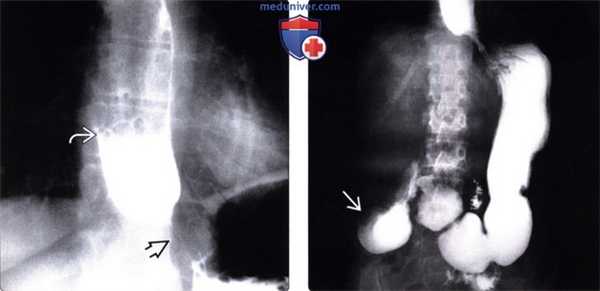

(Слева) На рентгенограмме пищевода, выполненной во время рентгеноскопии у мужчины 50 лет определяется отсутствие первичной перистальтики и глубокие, периодические третичные сокращения стенки пищевода. Просвет пищевода слегка расширен, видна стриктура в области пищеводно-желудочного перехода.

(Справа) На рентгенограмме, выполненной спустя два часа после рентгеноскопии этому же пациенту, определяется выраженное замедление прохождения контраста по тонкой кишке. Складки тощей кишки истончены и близко прилежат друг к другу, просвет кишки расширен, перистальтика выражена минимально: эти изменения являются классическими признаками «истощения» кишки.